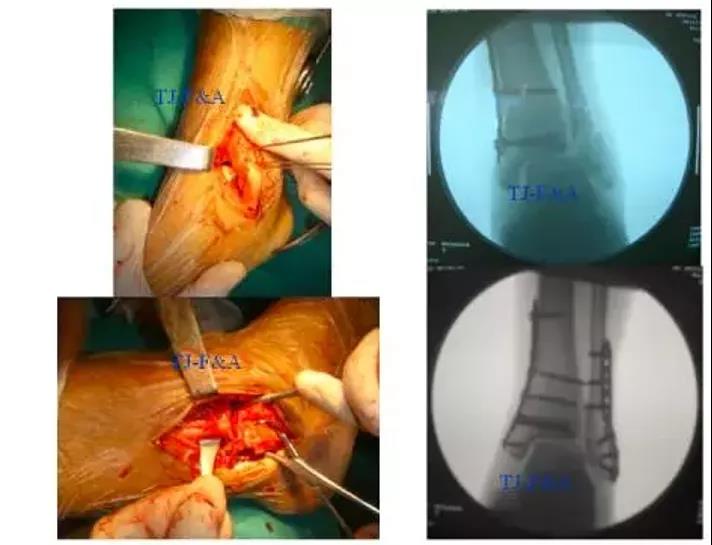

1.三角韧带探查,预置铆钉缝线2.后外侧切口复位固定外踝或后踝3.内侧切口复位固定内踝4.收紧三角韧带缝线5.下胫腓联合固定

术前

手术切口选择

术中复位顺序

术后DR